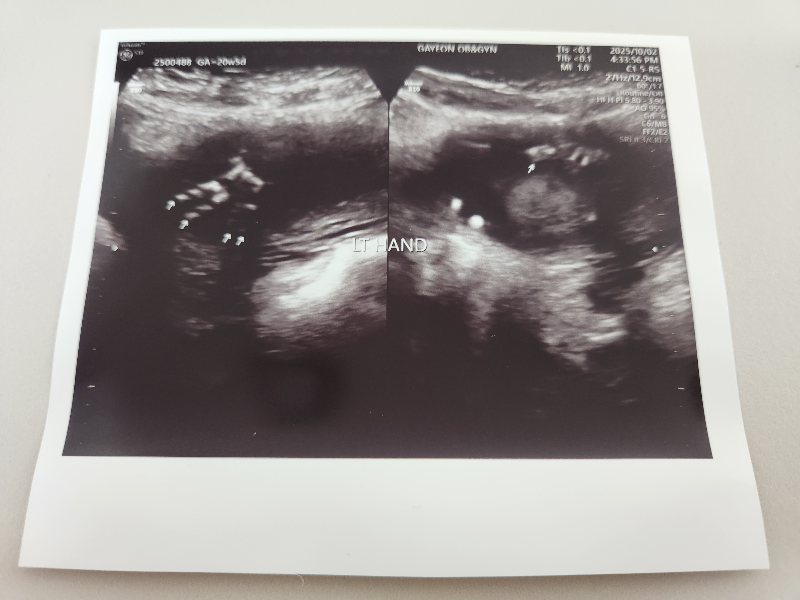

2차 정밀 초음파는 태아 신체 하나하나 다 꼼꼼히 확인합니다.

왼발 오른발 발가락을 확인합니다.

태아의 척추뼈도 확인합니다.

오른쪽 손 왼쪽 손 손가락을 다 확인합니다.